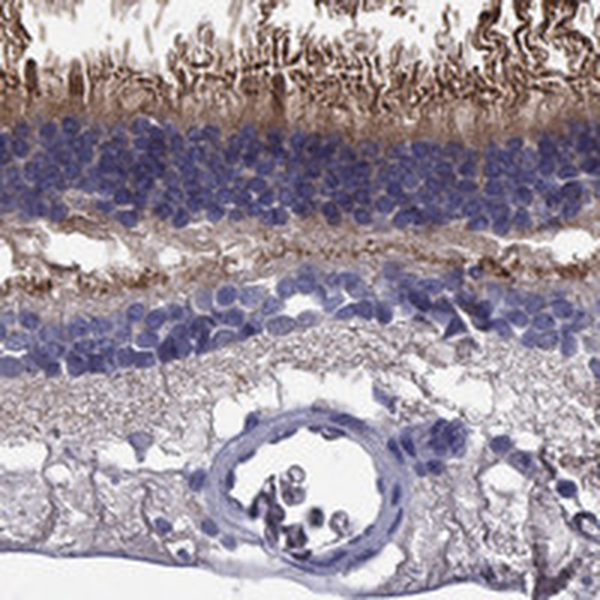

Immunohistochemical staining of human retina shows strong cytoplasmic positivity in photoreceptor cells.